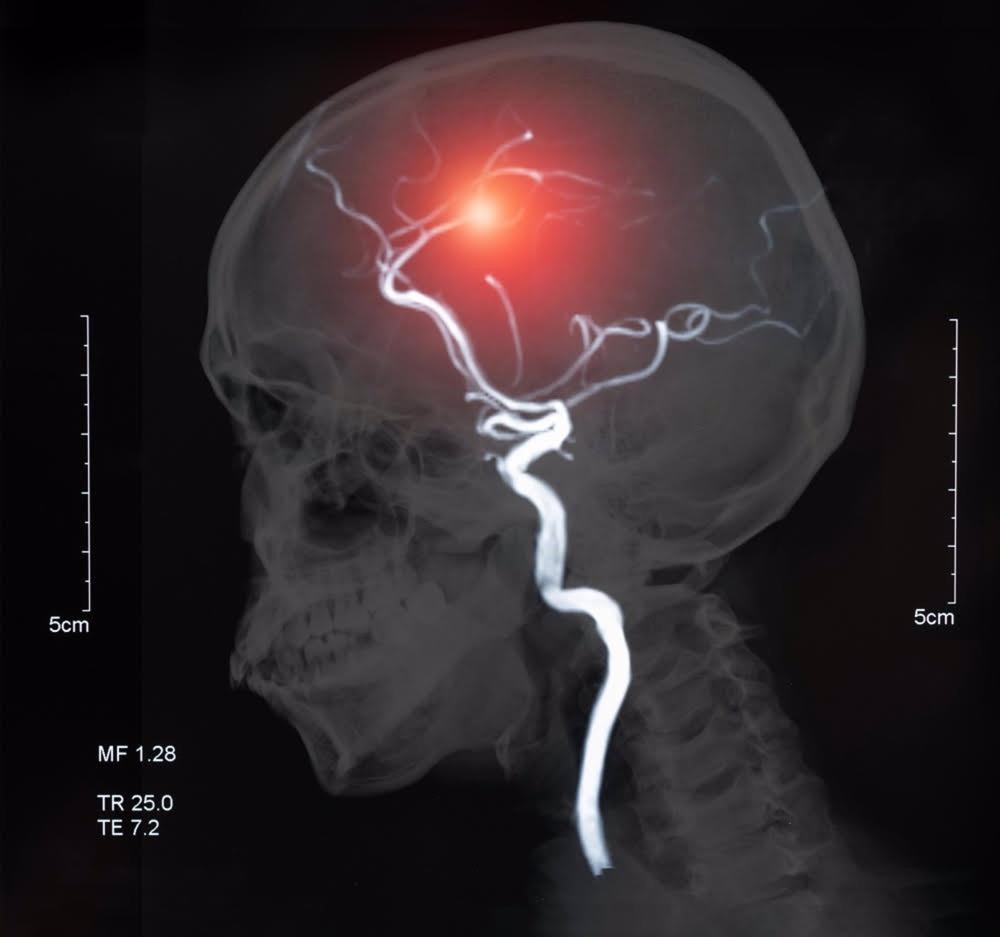

Se trata de un trastorno brusco en la circulación sanguínea del cerebro, ya sea por la obstrucción de una arteria (ictus isquémico, el 85% de los casos) o por un sangrado cerebral (ictus hemorrágico, el 15% de los casos). Puede afectar a cualquier edad, aunque es más frecuente a partir de los 65 años, y es la segunda enfermedad más frecuente en España, la principal causa de discapacidad y la segunda causa de muerte.

Según datos de la Sociedad Española de Neurología (SEN), cada año 110.000-120.000 personas sufren un ictus en España, de los cuales un 50 por ciento quedan con secuelas que les causan discapacidad o fallecen. Si bien es cierto, en los últimos 20 años, la mortalidad y discapacidad por ictus ha disminuido, gracias a la detección precoz y al control de los factores de riesgo.